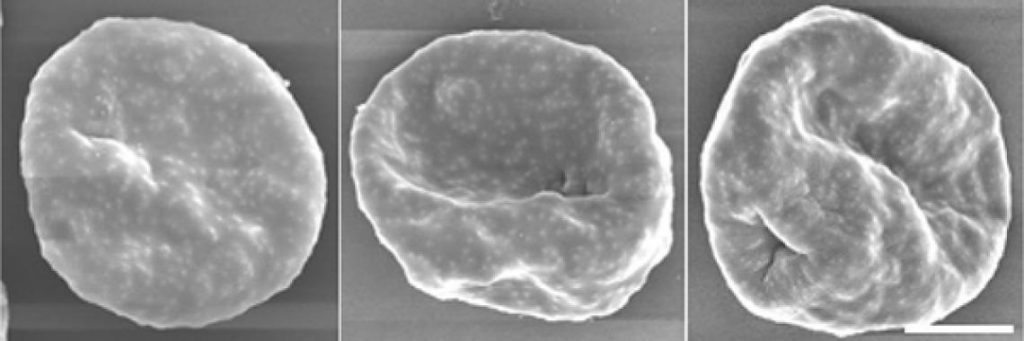

Malaria parasites transform healthy red blood cells into rigid versions of themselves that clump together, hindering the transportation of oxygen. The infectious disease affects more than 200 million people across the world and causes nearly half a million deaths every year, according to the World Health Organization’s 2018 report on malaria. Until now, however, researchers did not have a strong understanding of how the parasite so effectively infiltrated a system’s red blood cells.

The researchers focused on Plasmodium falciparum, the parasite that causes the most severe form of malaria. This parasite infects a host red blood cell, triggering the production of several proteins into the host cell’s cytoplasm—the bulk of the cell’s mechanics and the liquid in which they’re held, ultimately transforming the cell’s physical form. Not only does this transformation make the cells stick in place, out of the body’s immune response, it also helps the parasite travel to the surface of the cell and infect others. Together, the proteins work to proliferate the parasite, leading to the propagation of the malaria parasite.